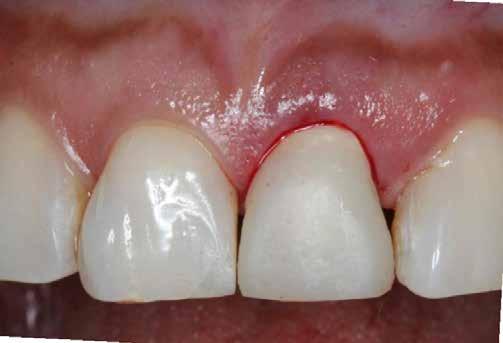

15. ábra: 1 nappal a műtét után. 16. ábra: 2 héttel a műtét után, szépen gyógyult a lágyszövet.

gömbfúróval, majd 2 mm-es előfúróval 13 mm-ig fúrtam� Amint az előfúrás sikeres, már nem nehéz tovább tágítani egészen 4,5 mm-ig [7]� Az implantátum ágyát ellenőriztük a megfelelő eszközzel, majd dezinfektáltuk ózonnal� Az implantátumot be lehet helyezni kézzel, racsni segítségével, vagy a megfelelő gépi behajtóval� Ennél az esetnél a primer stabilitást 40 Ncm-es behelyezési nyomatékkal sikerült elérni (9. ábra)� Kontrollröntgent (10. ábra) és egy üvegszálas csapot készítettünk a szék mellett extraorálisan� Egy dummy implantátumot használtunk, hogy könynyebb legyen az elkészítése (11. ábra)� A bepróbálás után az üvegszálas csapot RelyX Unicem-mel ragasztottuk be, az ideiglenes koronát szintén a rendelőben készítettük el a szilikonkulcs segítségével [8]� Az üvegszálas csapot vazelinnel izoláltuk és a koronát ideiglenes ragasztóval ragasztottuk, hogy el tudjuk távolítani a későbbiekben (12. ábra)� A kontrollröntgeneken (13. ábra) a csont jól megtartottnak tűnt, és az ideiglenes koronát át lehetett adni (14. ábra)� A korona sem okkluzióban sem artikulációban nem érintkezett az antagonista fogazattal� Egy nappal (15. ábra) és két héttel (16. ábra) később a lágyszövet szépen gyógyult�

4 hónapos gyógyulási időszakot követően átadtuk a végleges koronát (19. és 20. ábrák)� A lágyszövet továbbra is tökéletesen gyógyult maradt [9,10]� Az 5 éves kontrollon a csontszint teljesen megtartott volt (21. ábra)�